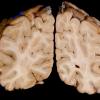

Methylene Blue Treatment